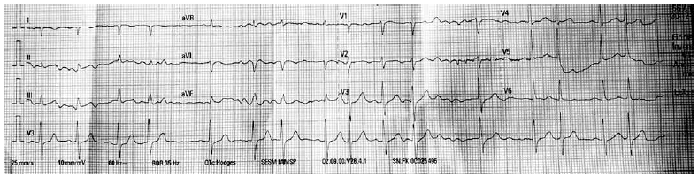

Durante o exame físico, foi observado que o ritmo cardíaco encontrava-se irregular. Foi realizado um eletrocardiograma, mostrado a seguir:

Foi feito o cálculo do intervalo QT corrigido pela fórmula de Bazett, 405 milissegundos. Assinale a alternativa correta a respeito do uso dos medicamentos que o paciente faz uso.

MANA, 85 anos, procura auxílio médico com história de sentir-se desanimada com fraqueza de membros inferiores. Vinha em uso de levotiroxina 50 mcg em jejum, omeprazol 20 mg em jejum, metoprolol 25 mg pela manhã, donepezila 5 mg/d, venlafaxina 150 mg/d e atorvastatina 20 mg/d. Durante exame físico, foi observada bradicardia, FC: 35 bpm. Foi realizado um eletrocardiograma, mostrado a seguir.

Assinale a alternativa que mostra qual associação medicamentoso pode justificar as alterações encontradas.